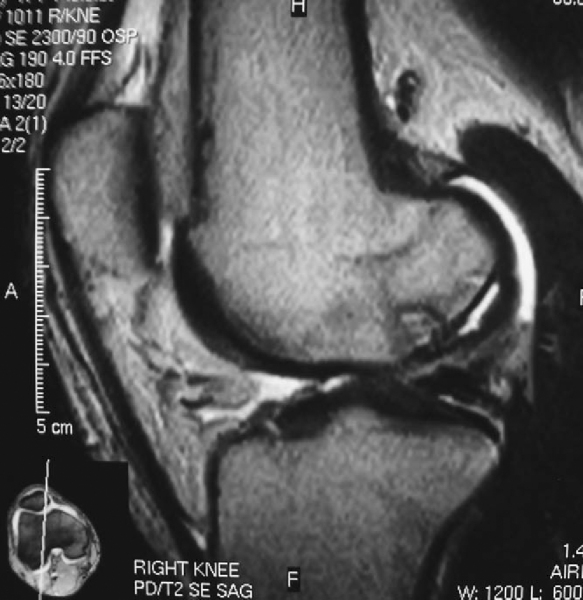

Standard (nonarthrographic) magnetic resonance imaging is the most informative imaging modality in the preoperative work-up. It reliably indicates lesion location, size, depth, and, most important, stability. The presence of one or more of the following four magnetic resonance criteria has been shown to offer up to 97% sensitivity and 100% specificity in predicting lesion stability. High signal is defined as signal intensity equal to that of fluid and greater than the signal intensity of adjacent fat. [6] [7] [8]

| • | Thin, ill-defined or well-defined line of high signal intensity 5 mm or more in length at the interface between the osteochondritis dissecans lesion and the underlying bone ( Fig. 53-2 )  |

Figure 53-2   |